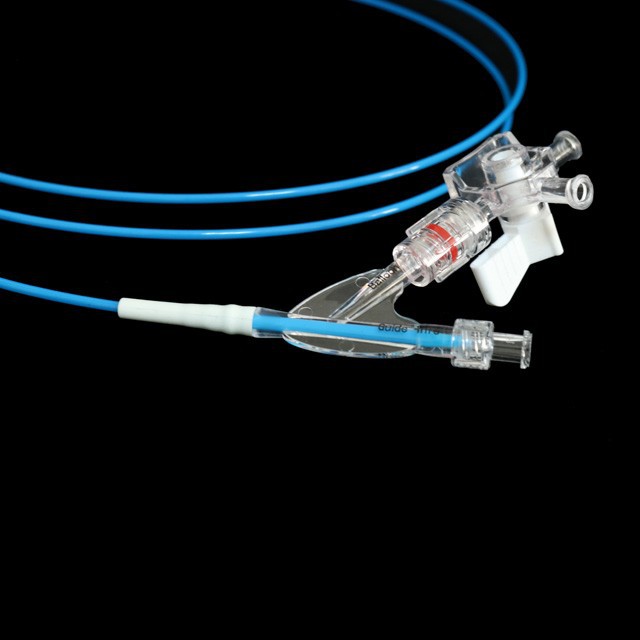

●Tað er hóskandi til vaksin og ungdóm í dilatatiónsvirkseminum av meltingarvegstriktinum undir endoskopum.

maður

●Pre-input 0.035"leiðaratráður við mjúkum oddi og merki,sum er lættari at meta um longdina á innaru duty-tráðinum.